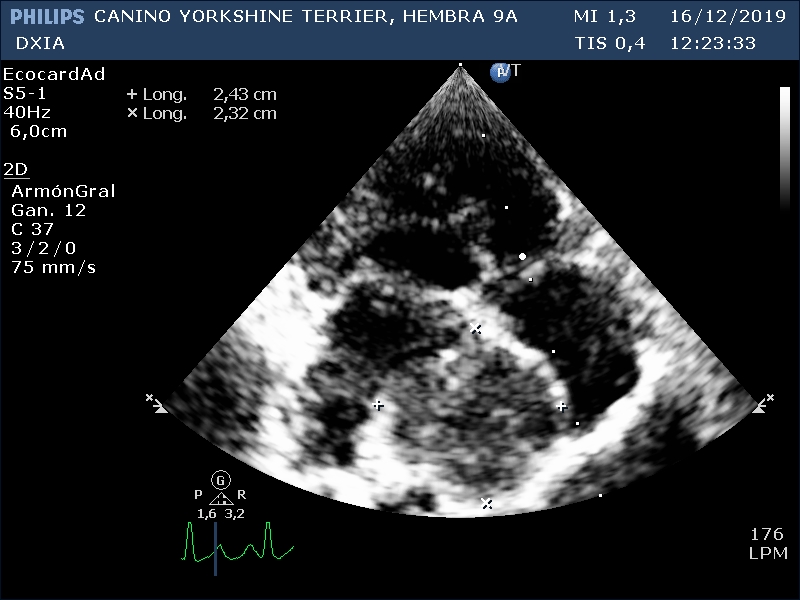

Corte apical izquierdo 4 cámaras. Se observa estructura hipoecogénica en zona del septo interauricular. No dilatación de ventrículos. No cambios en grosores de las paredes cardiacas. No presencia de derrame pericárdico.

Corte apical izquierdo en 4 cámaras